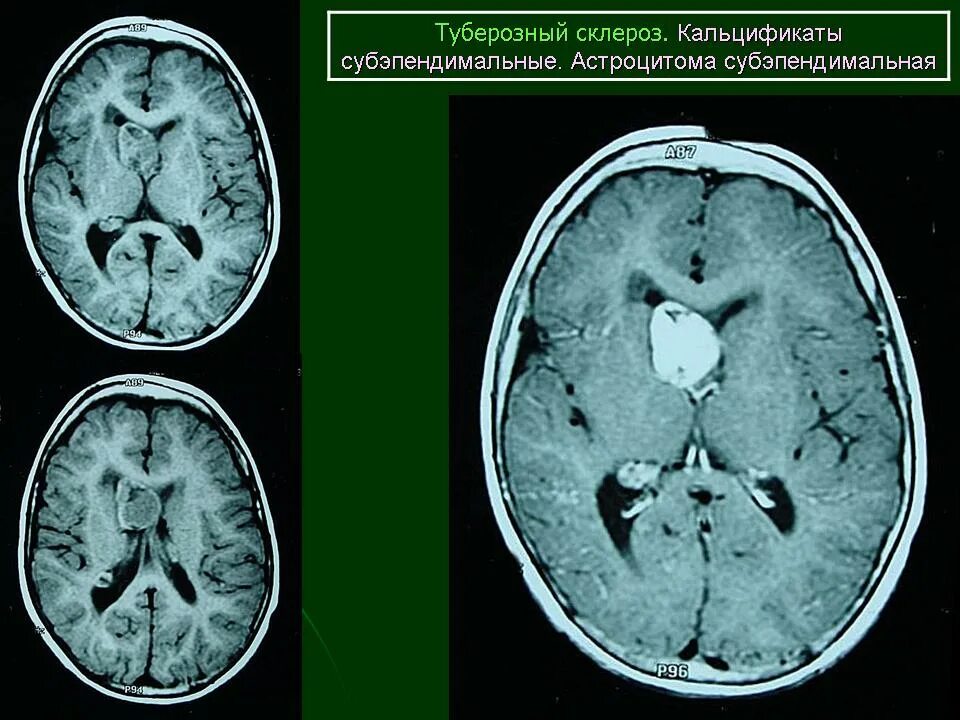

Туберкулезный склероз